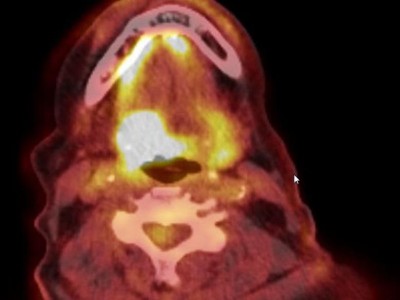

Eine ältere Frau schaut in die Ferne/© RgStudio / Getty Images / iStock (Symbolbild mit Fotomodell), Bestrahlungsplans einer Wirbelsäulenmetastase eines oligometastasierten Prostatakarzinoms/© Springer Medizin Verlag GmbH, Immuncheckpointinhibitoren binden an Krebszelloberflächenproteine /© Juan Gärtner / stock.adobe.com, Arzt misst Blutzucker per Glucometer/© geargodz / Stock.adobe.com (Symbolbild mit Fotomodell), Ein Anatomie-Modell des Kopfes in der HNO-Praxis/© peakSTOCK / Gettty Imgaes / iStock (Symbolbild mit Fotomodellen), Larynxkarzinom/© Springer Medizin, Tropf in Krankenhaus/© Amornrat Phuchom / Getty Images / iStock, Infusionstropf im Krankenhaus /© Trsakaoe / stock.adobe.com, Zytologischer Abstrich bei gynäkologischer Untersuchung/© Iryna / stock.adobe.com (Symbolbild mit Fotomodell), Pembrolizumab-Modell (Illustration)/© Kateryna_Kon / stock.adobe.com, Plattenepithelkarzinom des Oropharynx/© Springer Medizin Verlag GmbH, Tumor im linken Kleinhirnbrückenwinkel und inneren Gehörgang (linkes Bild) und Tumor am Foramen jugulare (rechtes Bild)/© Springer Medizin, Frau erhält Infusion/© Eakkachai / Stock.adobe.com (Symbolbild mit Fotomodell), Raumforderung im Ohr/© Franzen A M und Coordes A / all rights reserved Springer Medizin Verlag GmbH, Blumenkohlartiger Knoten am Hinterkopf/© Winkler D. et al. doi.org/10.1007/s00105-024-05437-1 unter CC-BY 4.0, 18-FDG-PET-Fusions-CT vom Kopf/© Sheila Büchel u. Markus Jungehülsing doi.org/10.1007/s00106-024-01459-2 unter CC-BY 4.0, VMAT-Bestrahlungsplan einer definitiven Radiochemotherapie eines linksseitigen, lokal fortgeschrittenen Tonsillenkarzinoms/© Schnellhardt, S et al. / all rights reserved Springer Medizin Verlag GmbH, Search Icon, Einem Mann wird Blut abgenommen/© auremar / stock.adobe.com (Symbolbild mit Fotomodellen), Frau wird Blut abgenommen/© andresr / Getty Images / iStock (Symbolbild mit Fotomodellen), Eine Frau erhält eine Chemotherapie/© peopleimages.com / stock.adobe.com (Symbolbild mit Fotomodell)